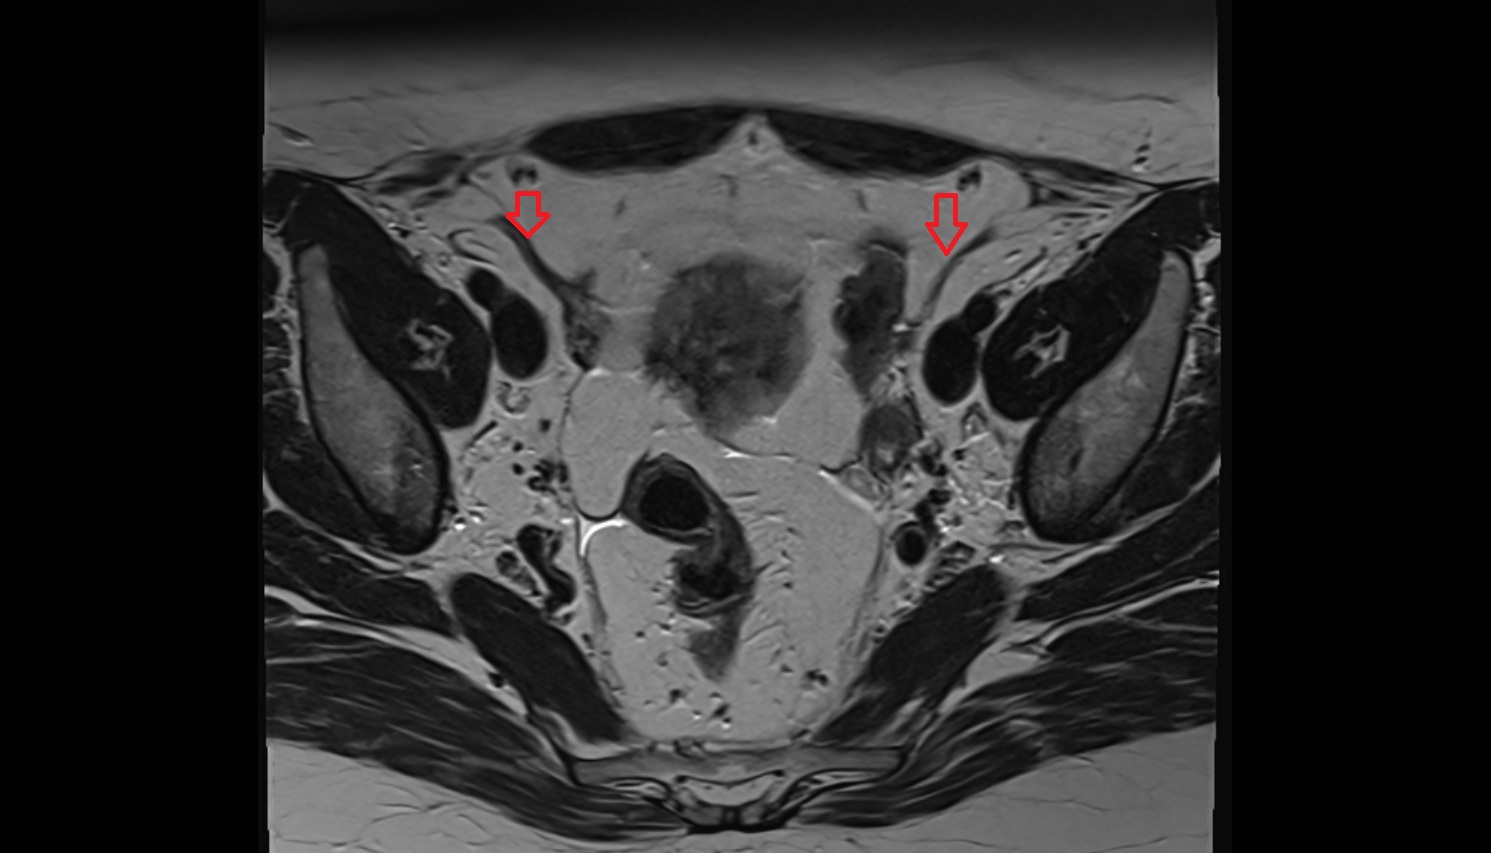

- Intermediate lacunar external iliac lymph nodes

- External iliac lymph nodes

- Obturator lymph nodes